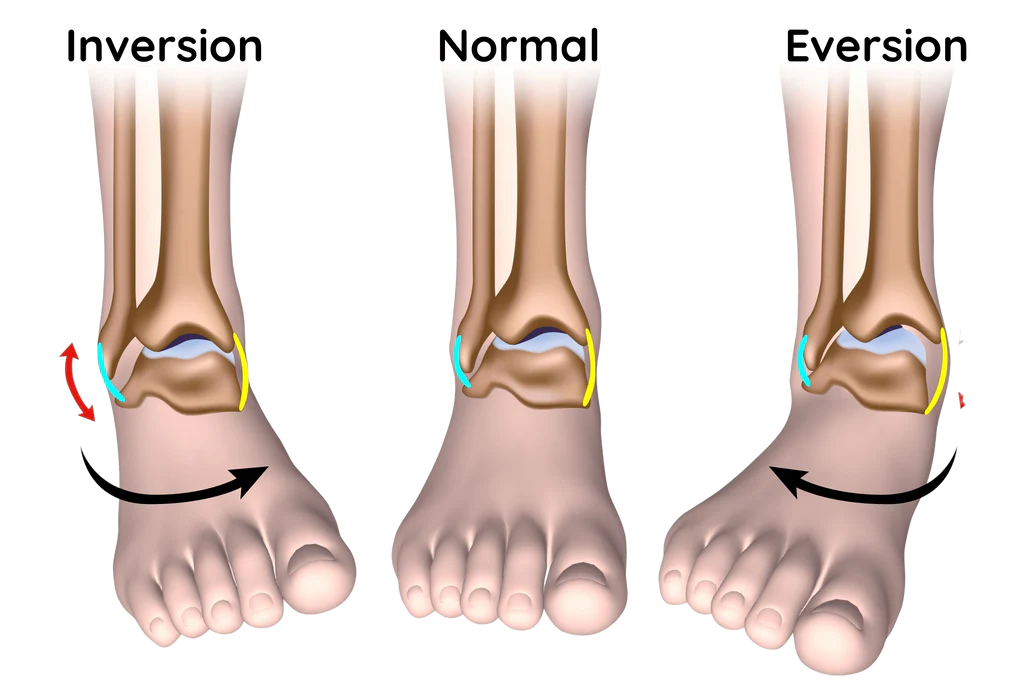

| Underbenets rotation | Lateral depression kan ge extern rotation av tibia | Påverkar fotens ställning (pronation) |

| Fotled | Felställd tibia → talus vinklas, foten faller inåt | Valgus-fot / överpronation |

En breddad, insjunken lateral tibialplatå → valgusfel → yttre sidan ”sjunker” → inre sidan får översträckning → hela underbenet roterar och foten pronerar.

När underbenet står i valgus och rotation:

- Foten tvingas kompensera för att du ska kunna stå rakt.

- Det leder till:

- Överpronation (foten faller inåt)

- Inåtrotation av fotvalv och talus

- Smärta i fotled, plantarfascit, peroneus-överbelastning

- Instabilitet i fotleden och ibland smärta vid fibulaspetsen

Överpronation i foten, felställning i fotled